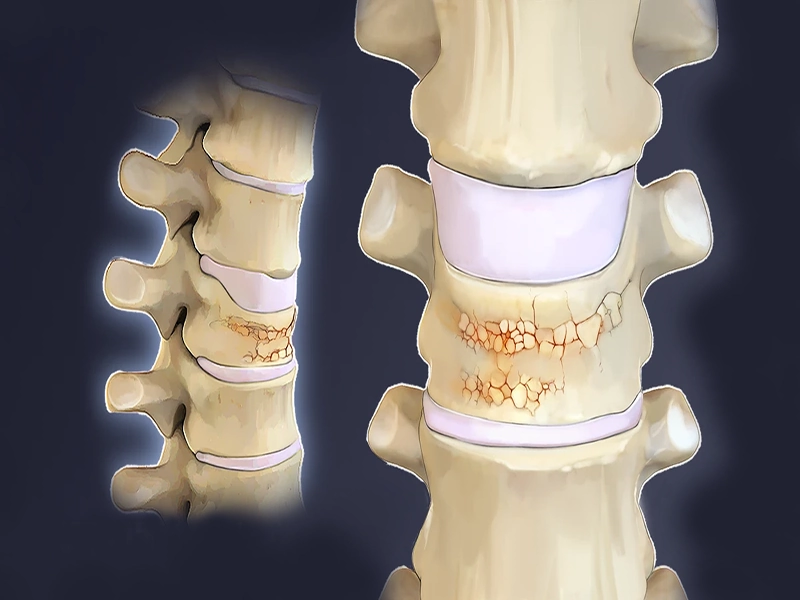

پوکی استخوان یا استئوپروز، بیماری خاموشی است که بدون علامت خاصی، استخوانها را شکننده و ضعیف میکند. در افراد مسن، به ویژه زنان پس از یائسگی، یکی از شایعترین پیامدهای این بیماری، شکستگی مهرههای ستون فقرات است؛ شکستگیهایی که حتی ممکن است با عطسه یا خم شدن ساده رخ دهند....

شکستگی مهره کمر چگونه رخ میدهد؟ ستون فقرات یکی از مهمترین ساختارهای بدن انسان است که هم وظیفه محافظت از نخاع را برعهده دارد و هم به ما اجازه میدهد صاف بایستیم، حرکت کنیم و تعادل خود را حفظ کنیم. این ستون محکم اما انعطافپذیر، از ۳۳ مهره تشکیل شده...